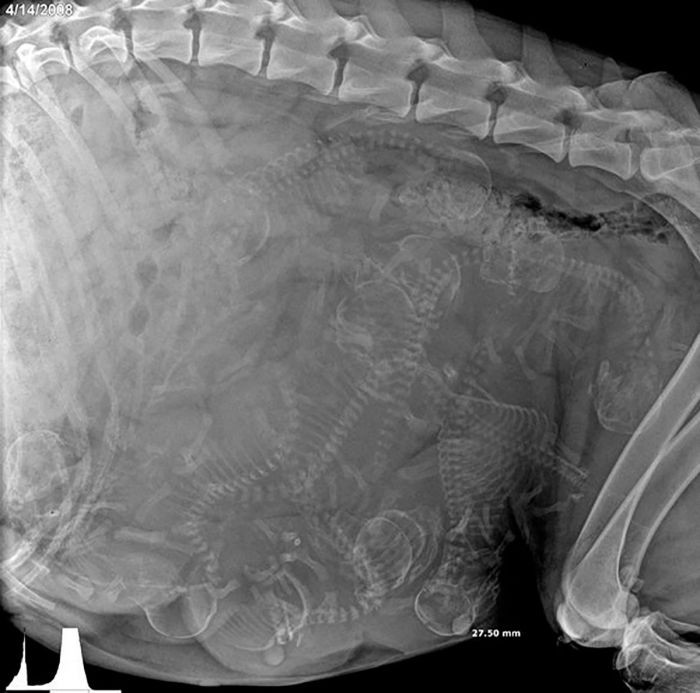

A day in the life of a pregnant Dog.